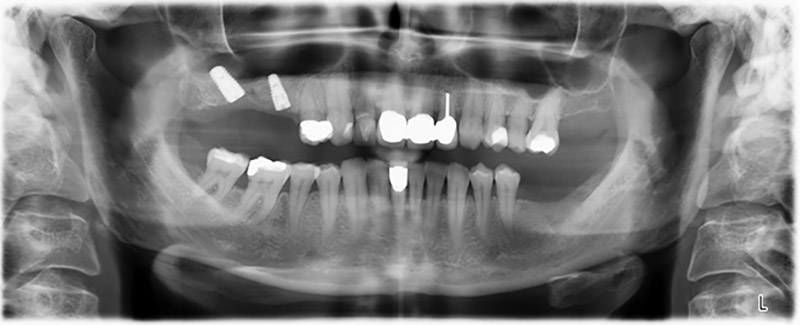

About six months after teeth 16 and 14 were extracted, a digital volume tomography (DVT, Planmeca) examination was performed for planning and risk minimization purposes. It clearly showed that the bone had not regenerated to the desired volume (Fig. 2 to 7).

A sinus floor elevation is required in both region 16 and region 14 to guarantee a fixed restoration based on at least two implants. Relatively large-scale bone augmentation is required due to the residual bone volume being extremely low in this case. Major bone augmentation procedures are invasive and linked to higher patient morbidity, as well as being time-consuming and expensive. It is more difficult to predict the results of the treatment and the risk of failure is increased. The patient was informed of the increased risk and was offered a removable solution, which she consistently rejected.

To restrict the augmentation to region 14, and in consultation with the patient, it was planned that implant 16 would be placed, inclined, in the dorso-cranial direction (Fig. 8).